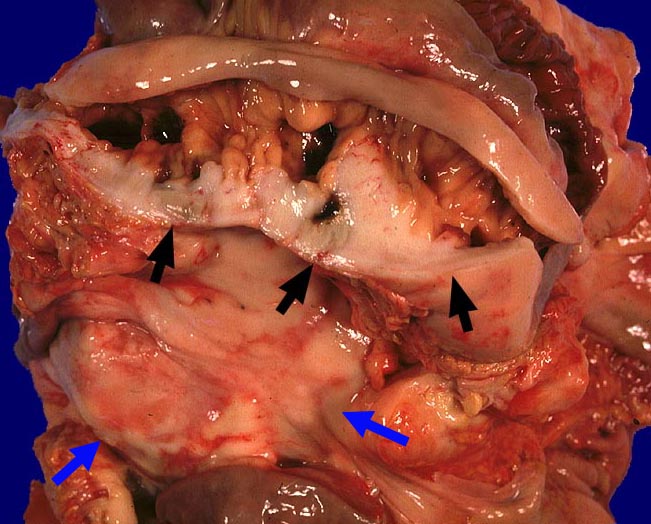

PathoPic ID 424 - Diffuses grosszelliges B-Zell-Lymphom (WHO)

Diffuses grosszelliges B-Zell-Lymphom (WHO)

Mesenterium

Darm, Anus

Eröffnetes Jejunum mit anhaftendem Mesenterium. Das

►

Mesenterium und die

Jejunumwand sind diffus lymphominfiltriert.

Zusatzbefund

Befall abdominaler Lymphknoten.

St.n. Chemotherapie.